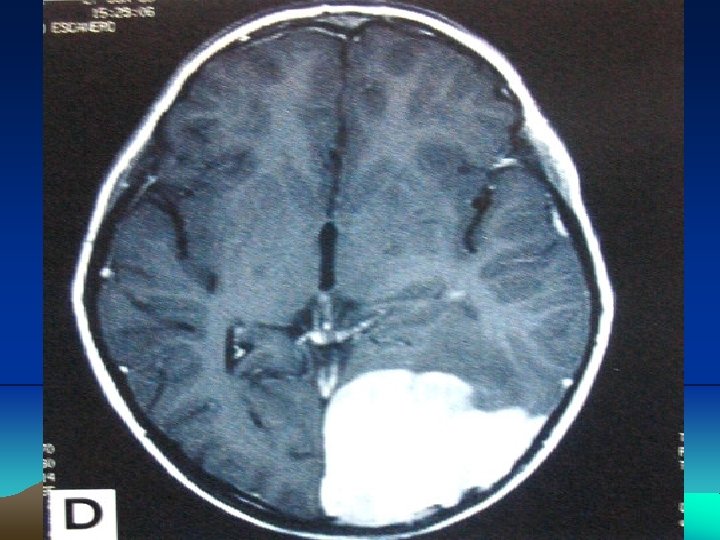

CNS lymphoma may affect people whose immune system is not working properly. for example, after organ transplants, or in people with HIV

primary CNS lymphoma. : The most common site for a CNS lymphoma is the cerebrum The areas of the brain

CNS lymphoma The symptoms and signs of CNS lymphoma are often related to increased intracranial pressure ( ICP ), e. g. headache, mental change, or focal neurological deficits Notably, only 5% of CNS lymphoma patients experienced inner ear symptoms such as vertigo, tinnitus or progressive hearing loss [9]. Thus, clinically, vertigo accompanied by progressive hearing loss rarely occurs in CNS lymphoma.